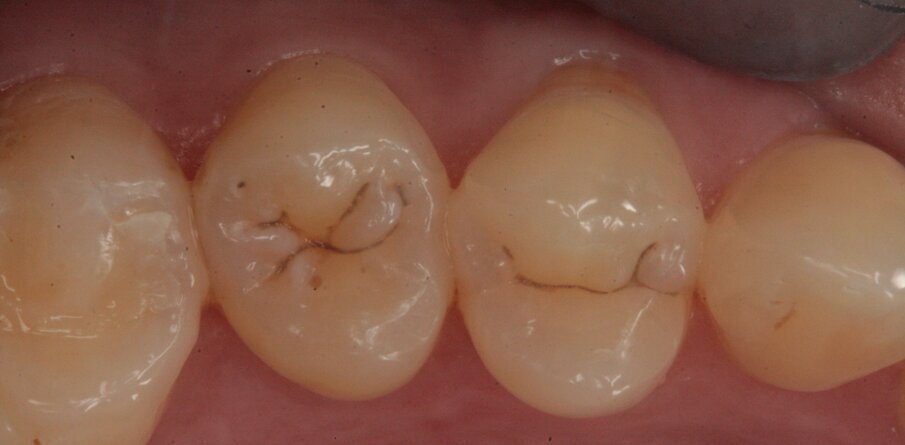

Gli elementi da trattare, 36 e 37, all’esame obiettivo presentano leggeri solchi intaccati dal processo carioso (Figg. 19, 20); clinicamente la dentina viene interessata perciò si procede al restauro mediante due masse, una dentinale e una smaltea (Figg. 21, 22).

Fig. 19_Restauro presente nell’elemento 37 e solchi interessati dal processo carioso dell’elemento 36.